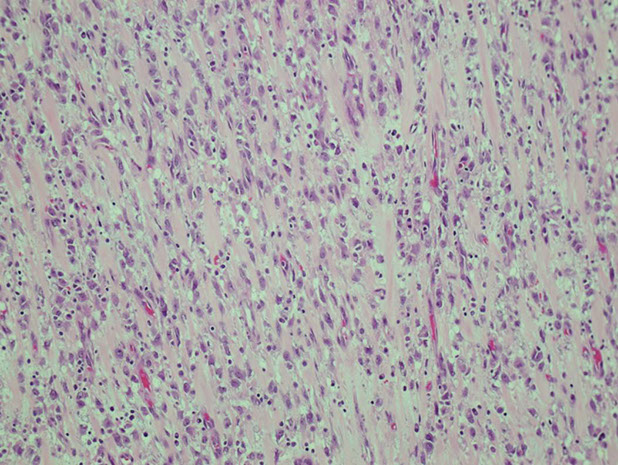

Desmoid fibromatosis with long sweeping fascicles

Desmoid fibromatosis with medium-sized BV